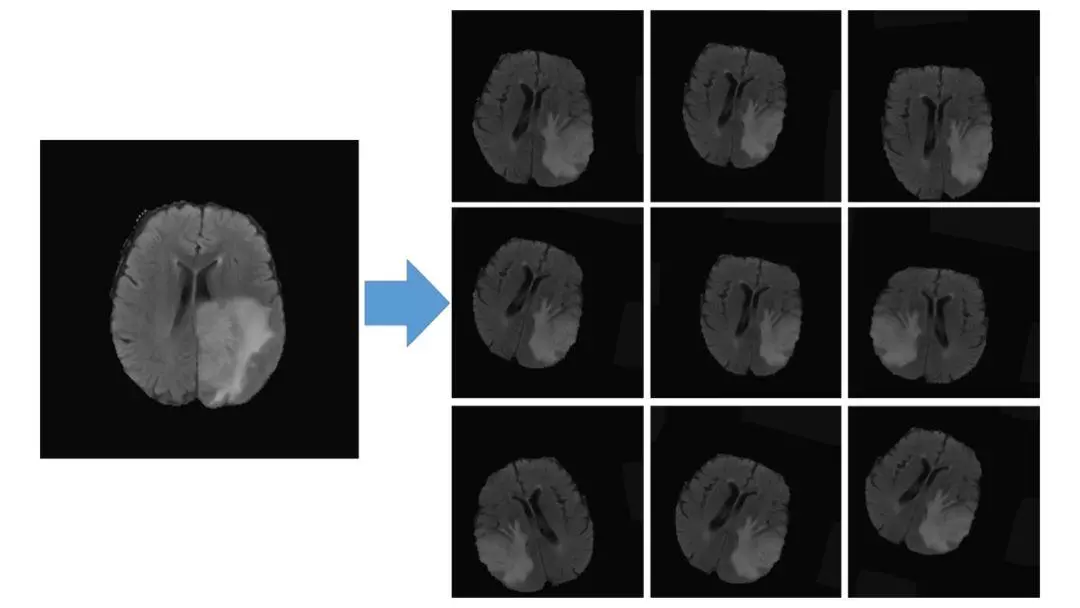

这个例子用到了 BRATS 2017数据集 ,数据扩张处理如下图所示: